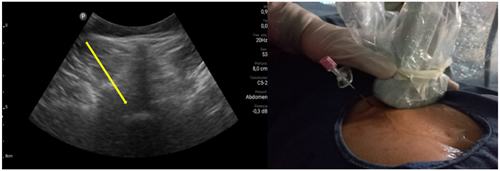

Pacientes y métodos: Un total de 25 pacientes con dolor radicular lumbosacro fueron seleccionados para recibir inyecciones epidurales interlaminares de esteroides en posición decúbito dorsal, utilizando la técnica ecoguiada en plano, en tiempo real, en eje corto o transversal. En todos los casos, un epidurograma de control fue realizado previo a la inyección de la solución de esteroides. El rendimiento de la técnica fue estudiado mediante la tasa de éxito de la misma, entendido como éxito a la obtención de un epidurograma sin necesidad de abandonar la técnica ecográfica en un tiempo menor a 10 minutos. El rendimiento del procedimiento fue estadísticamente evaluado por el método de la suma acumulativa (CUSUM), y la curva de aprendizaje aplicando este método fue construida.

Resultados: La distancia promedio desde la piel al complejo posterior evaluada por el escaneo ecográfico previo al procedimiento fue de 6,7 ± 1,8 cm. De los 25 procedimientos realizados, en 21 se alcanzó el espacio epidural sin ayuda de la fluoroscopia, en un tiempo promedio de 4,8 ± 1,2 minutos. Esto constituye una tasa de éxito del 84 %. En los cuatro procedimientos restantes el espacio epidural fue alcanzado con éxito mediante el uso complementario de la fluoroscopia.

5. Karmakar MK, Li X, Ho A, Kwok WH Chui PT. Real-time ultrasound-guided paramedian epidural access: evaluation of a novel in-plane technique. Br J Anaesth. 2009;102(6):845-54.

6. Elsharkawy H, Saasouh W, Babazade R, Soliman LM, Horn JL, Zaky Sh. Real-time Ultrasound-Guided Lumbar Epidural with Transverse Interlaminar View: Evaluation of an In-Plane Technique. Pain Med. 2019;20(9):1750-5.

7. Wang Y, Wang, G, Ma D, Li H. Real-Time Ultrasound-Guided Paramedian Epidural Access Using a Paramedian Transverse Oblique Scan: A Prospective Case Series. J Anesth Perioper Med 2018;5:70-6.

8. Li H, Kang Y, Jin L, Ma D, Liu Y, Wang Y. Feasibility of ultrasound-guided lumbar epidural access using paramedian transverse scanning with the needle in-plane: a comparison with paramedian sagittal scanning. J Anesth. 2020;34(1):29-35.